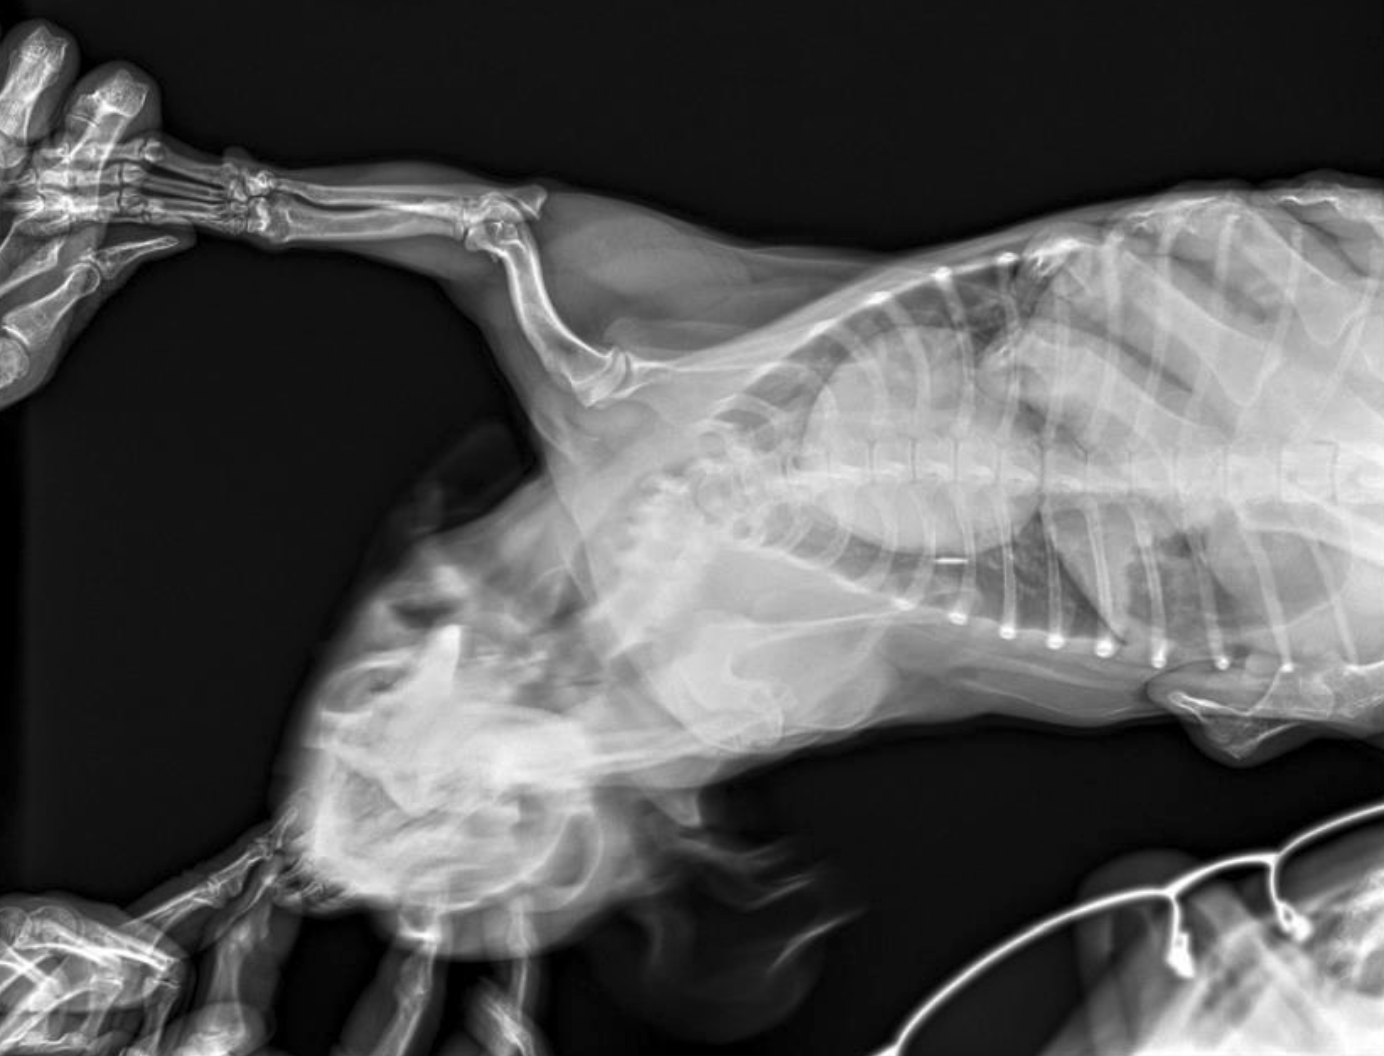

🖼️ My favourite image *(MRI, CT, US, Rads)*

File

Image